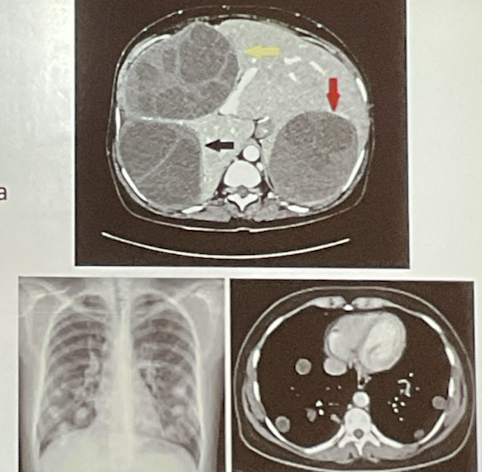

como se dx eschinococcus granulosus?

A

• rx

• serología

por qué se manifiesta la enfermedad por eschinococcus granulosus?

quistes